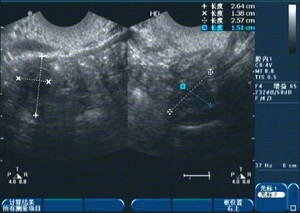

1、診斷:醫(yī)生會(huì)通過(guò)詢(xún)問(wèn)病史、體檢及輔助檢查(如超聲檢查、激素檢測(cè)等)來(lái)確定診斷。